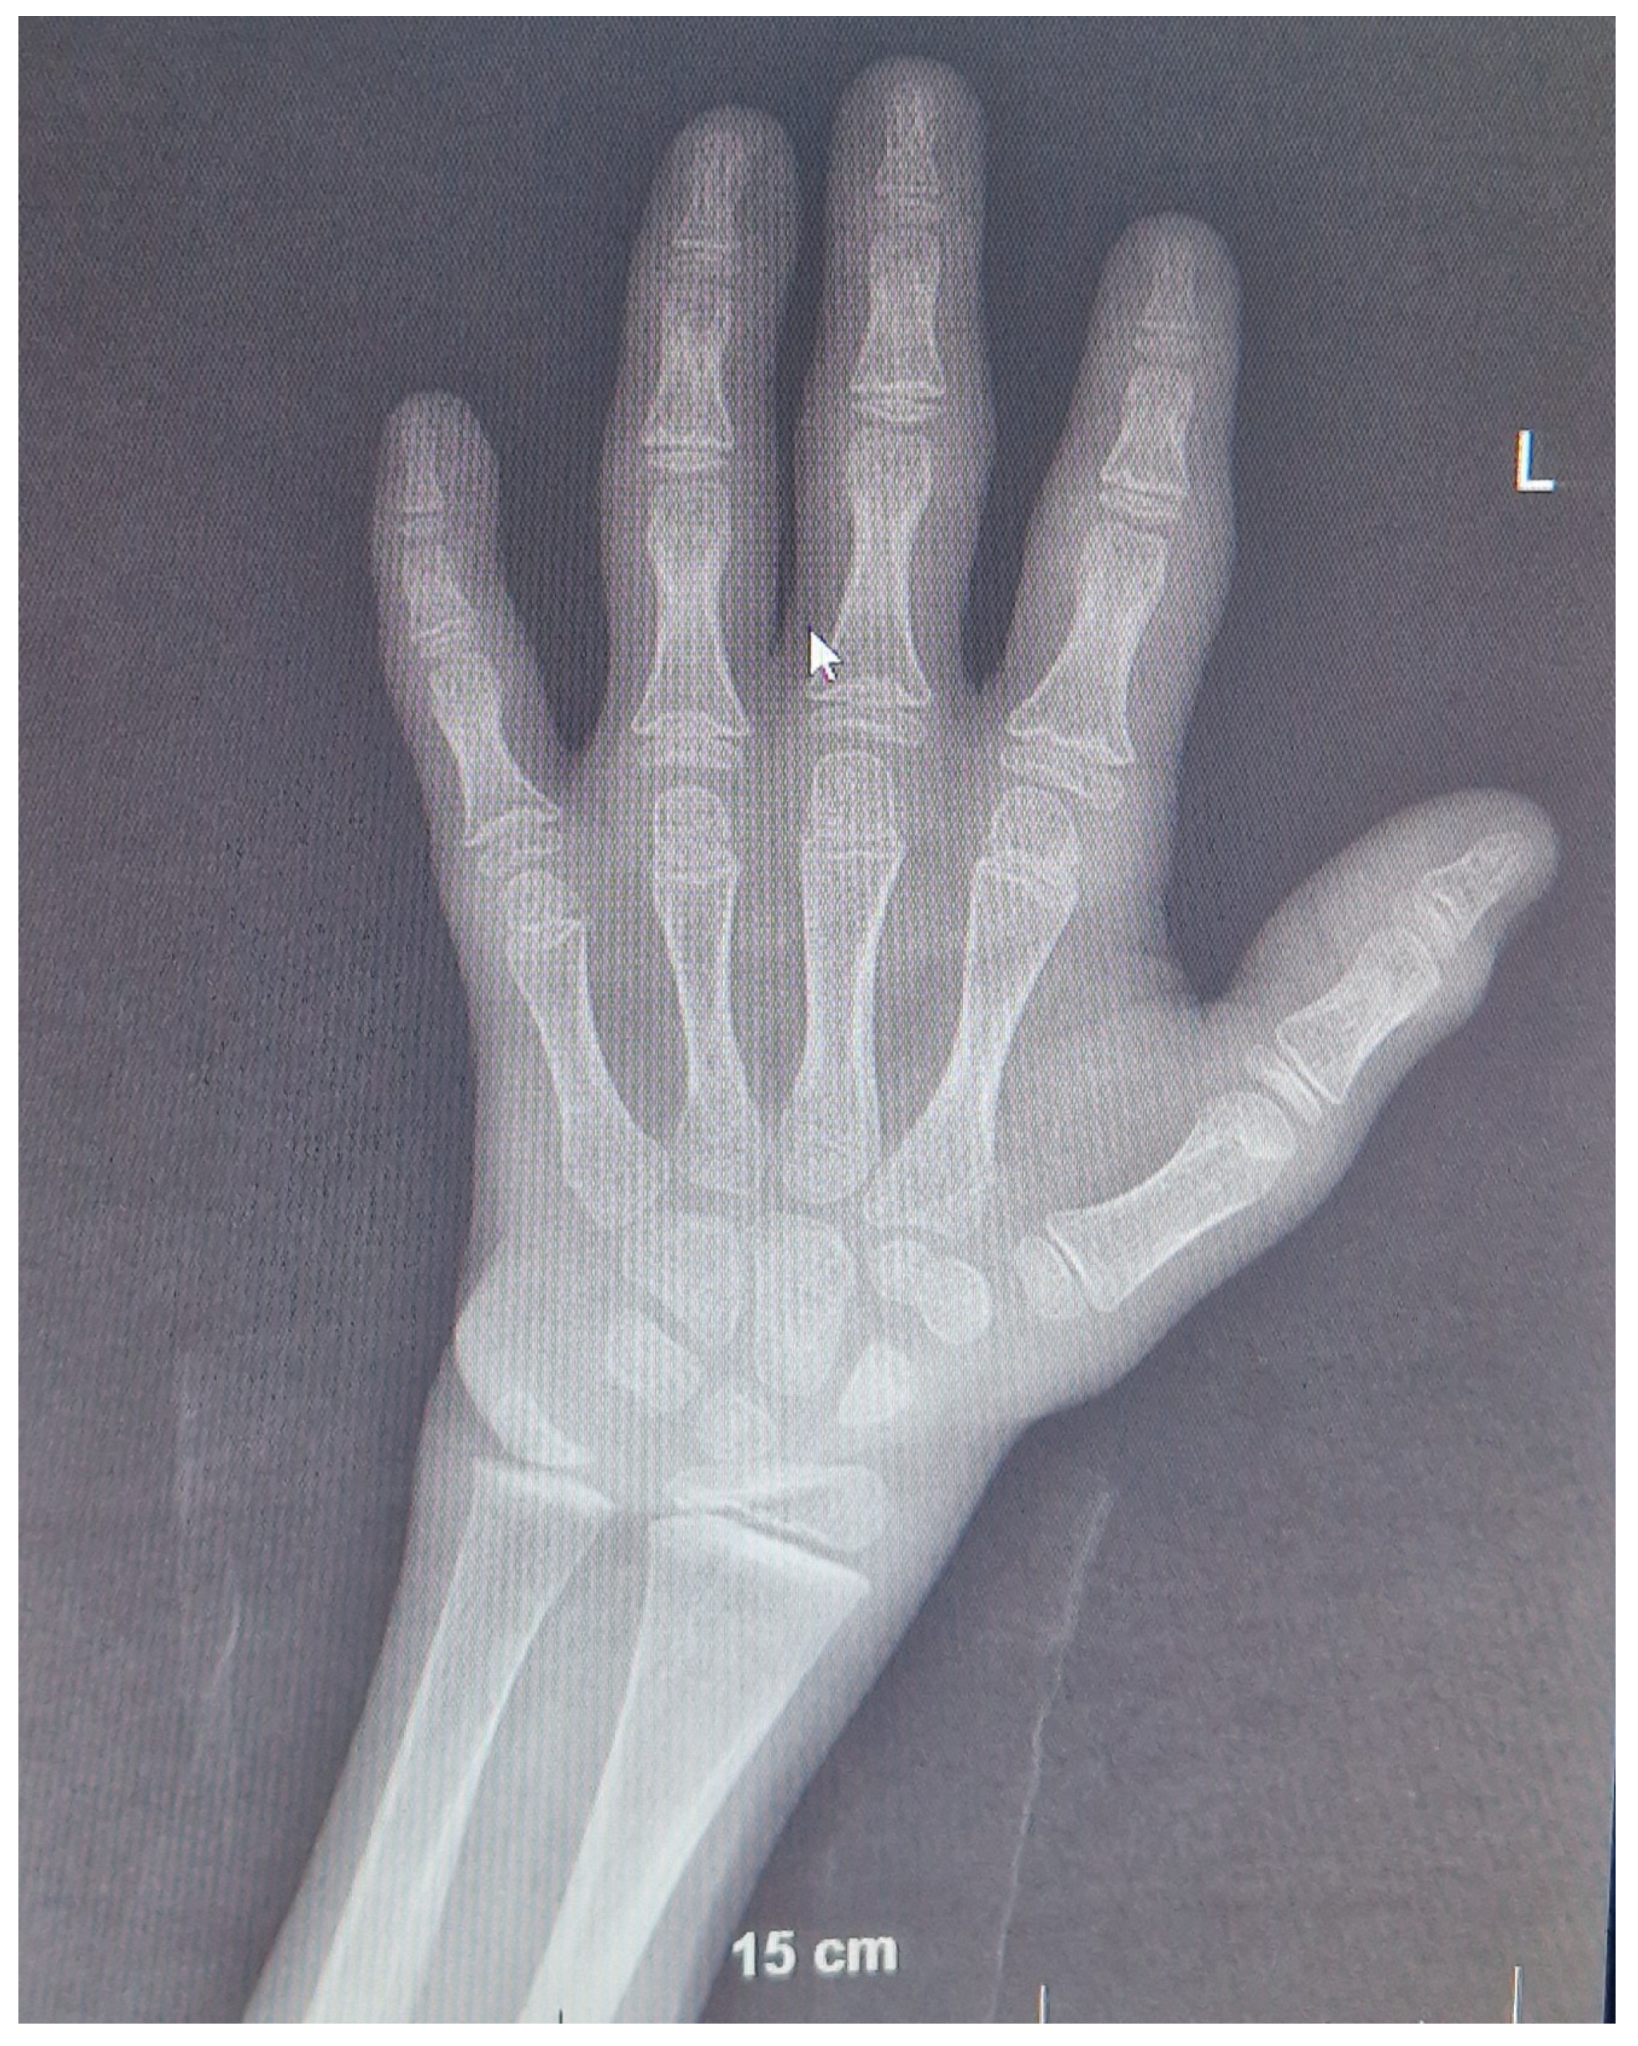

The total 25-hydroxyvitamin D3 was low, while PTH-intact was high (Table 1). According to the Greulich and Pyle method, the bone age (BA) was severely delayed (9 months at the chronological age of 3 years, 9 months), and bone radiograms showed alterations that were consistent with severe rickets (Figure 2). There were no signs of nephrocalcinosis. Ultrasound (US) examination confirmed bilateral cryptorchidism. Pachygiria, dilated Virchow–Robin perivascular spaces, and a normal pituitary body and stalk were all seen on the magnetic resonance imaging (MRI).

Figure 2. Radiogram of the wrists of the patient at 3 years 7 months of age showing severe rickets. Diffusely reduced bone mineralization, widened metaphyseal surfaces of the distal radius, ulna, and metacarpal bones with uneven contours to the epiphyseal plates are evident, as well as expanded growth plates (cupping) with soft tissue thickening of the wrist and distal metacarpal bones. Bone age measured by the Greulich and Pyle atlas method corresponds to that of a 9-month-old boy and is more than 2SD behind the chronological age.

The patient is currently 9 years 6 months old and has made remarkable improvements in both his physical (he walks by himself with some hand support) and mental development (he has 10–20 words in his vocabulary). Throughout the monitoring period, kidney function remained stable (Table 1). The current BUN serum level is 6.5 mmol/L, the creatinine level is 71 mmol/L, K+ is 4.3 mmol/L, Ca2+ is 2.5 mmol/L, and pH is 7.45. Radiograms of the wrists are normal with adequately progressing BA (8 years 6 months at the chronological age of 9 years 6 months, Figure 3). Additionally, kidney US remained normal. Fluid intake increased to the normal level for body size, especially after introducing rhGH treatment.

Figure 3. Radiogram of the patient’s wrists at 9 years 6 months of age. Bone age corresponds to 8 years 6 months according to the Greulich and Pyle method, which is less than −2 SD behind the chronological age. No evidence of rickets was found.